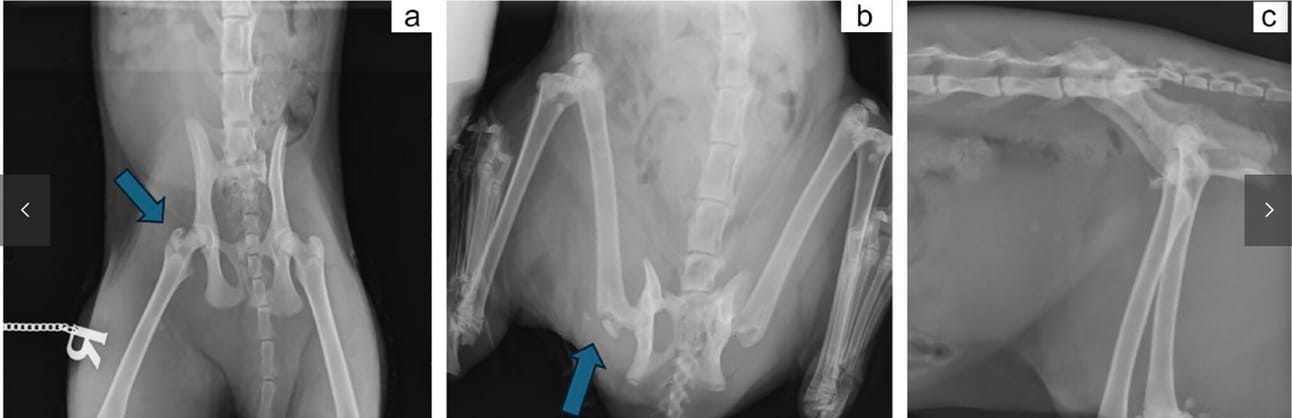

Case 14. (a) Extended-leg ventrodorsal radiograph of the pelvis showing a fracture of the right greater trochanter (blue arrow). This radiographic view was given a score of 2, as the fracture line is partially obscured by the neck of the femur. The cat also has ipsilateral sacroiliac luxation and a pubic fracture. (b) The same cat had a frog-leg ventrodorsal radiograph taken, which improved the radiographic accuracy for detecting the greater trochanteric fracture (blue arrow) and scored as 1. (c) Lateral radiographic view of the caudal abdomen and pelvis of the same cat. The greater trochanteric fracture in this view is very difficult to detect given the superimposition of the hemipelves, with the wings of the ilium obscuring the greater trochanteric fracture, and was given a score of 3